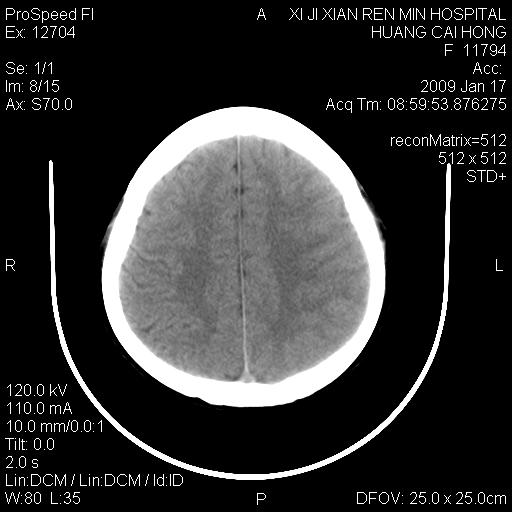

以下是引用zbp537在2009-1-19 13:54:00的发言:[br]首先考虑脑炎。[br]诊断依据:[br]1、患者较年轻。[br]2、有感冒病史。[br]3、左侧颞枕叶这么大一片低密度影,占位征象却不明显,不符合肿瘤特征,其内的高密度影为出血灶。

以下是引用xiaoniu在2009-1-19 13:29:00的发言:[br]左侧颞叶三角形低密度影,占位效应不明显,其内点片样高密都影,青少年患者,首先考虑:少突胶质瘤。因为有感冒病史,不能除外感染的可能。